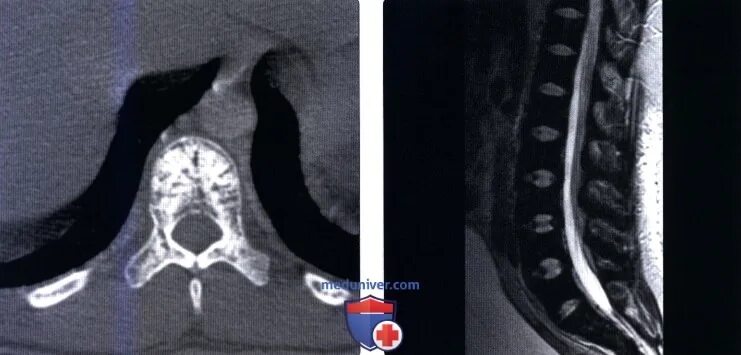

Остеосклероз позвоночника поясничного отдела